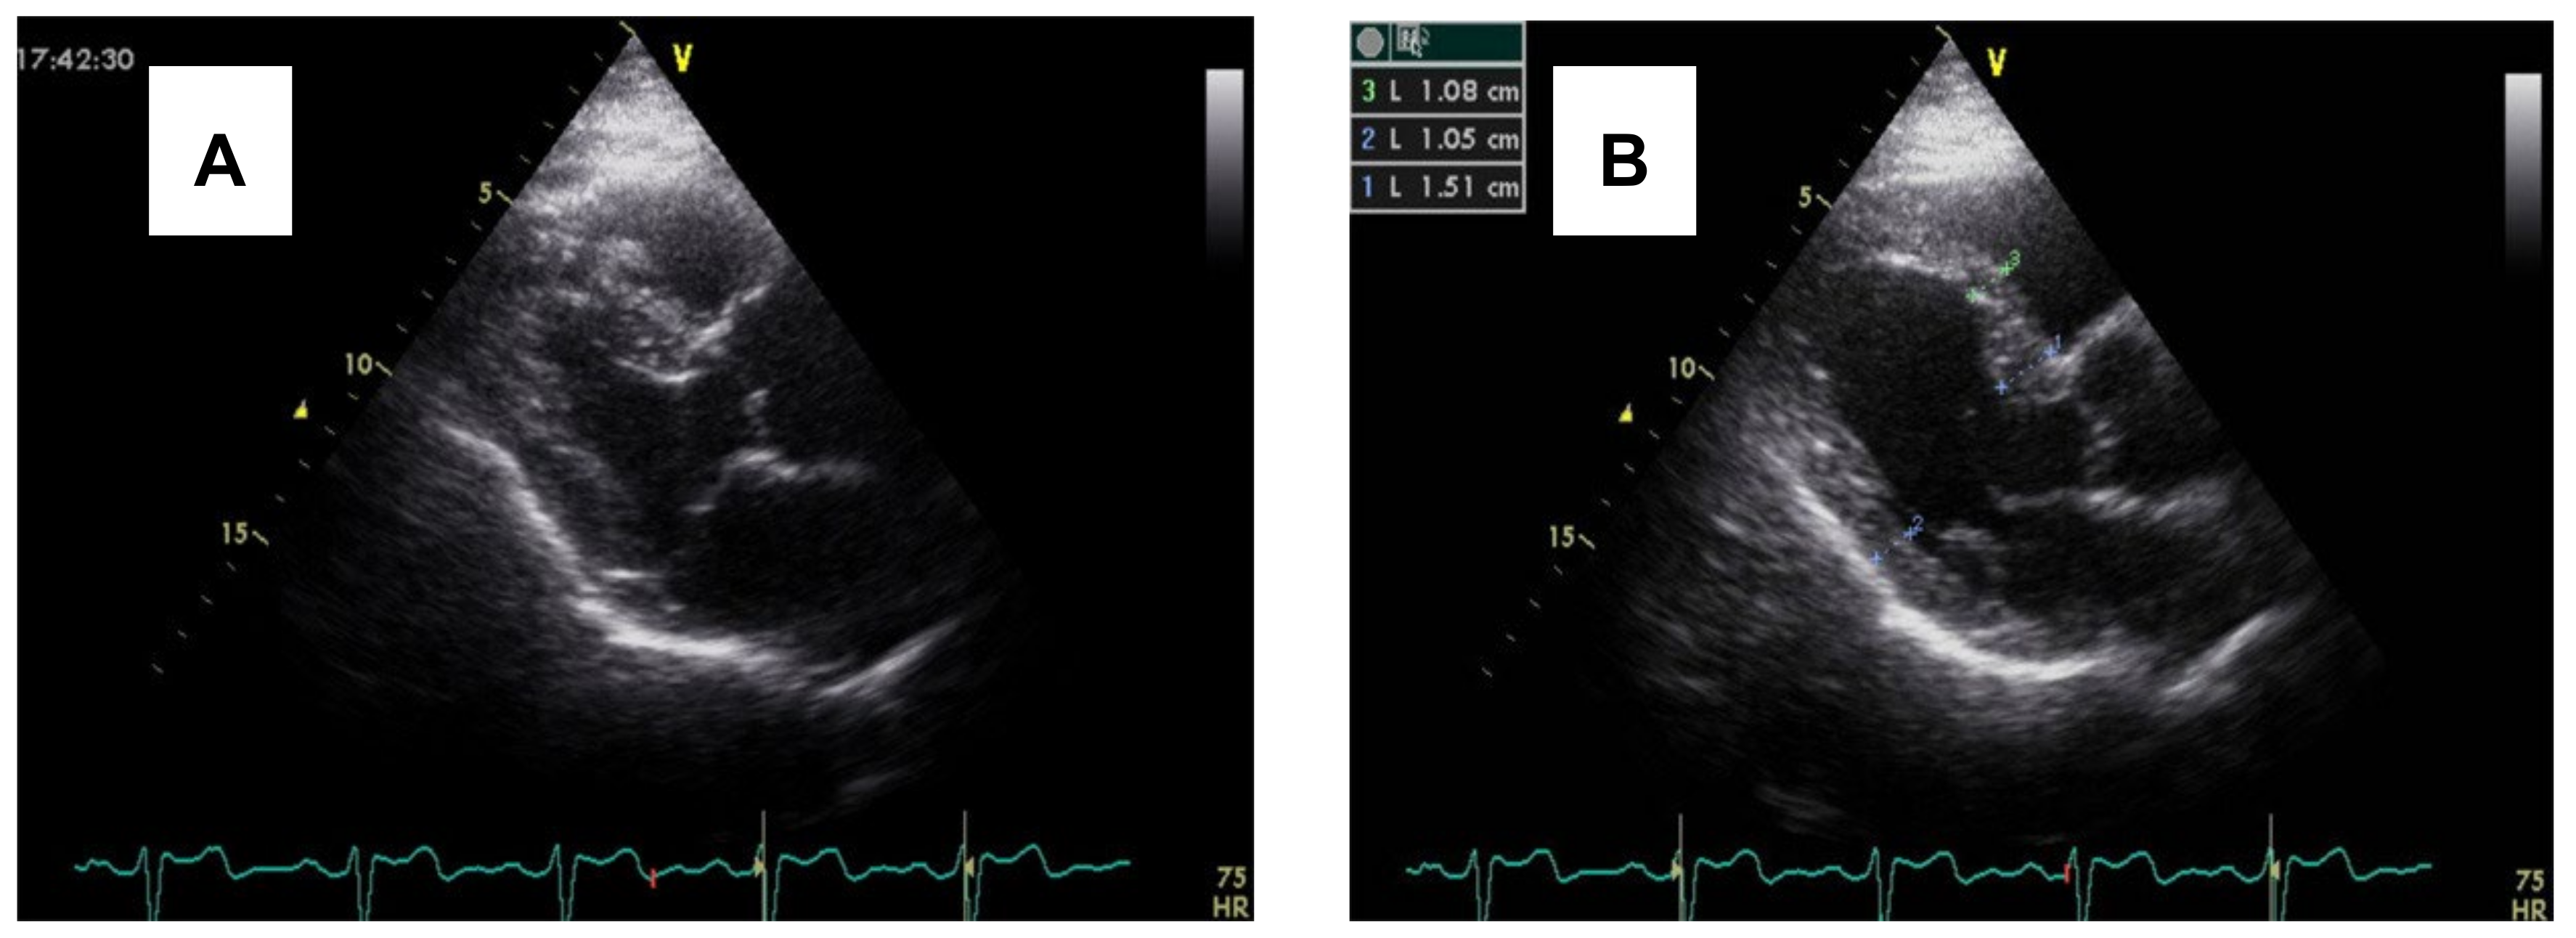

3.2. Imaging and Hemodynamic Observations

- Çağatay, B.; Yalçin, F.; Kıraç, A.; Küçükler, N.; Abraham, M.R. The Science Behind Stress: From Theory to Clinic, Is Basal Septal Hypertrophy the Missing Link between Hypertension and Takotsubo Cardiomyopathy? Stresses 2024, 4, 330–341. [Google Scholar] [CrossRef]

- Yalçin, F.; Çağatay, B.; Küçükler, N.; Abraham, T.P. Geomeric and Functional Aspects in Hypertension and Takotsubo: Importance of Basal Septal Hypertrophy. Eur. J. Prev. Cardiol. 2023, 30, 1996–1997. [Google Scholar] [CrossRef]

- Abuarqoub, A.; Garis, R.; Shaaban, H.; Khaddash, I.; Shamoon, F. Takotsubo Cardiomyopathy with Basal Hypertrophy and Outflow Obstruction in a Patient with Bowel Ischemia. Int. J. Crit. Illn. Inj. Sci. 2018, 8, 44–47. [Google Scholar] [CrossRef]

- Yalçin, F.; Muderrisoǧlu, H. Tako-Tsubo Cardiomyopathy May Be Associated with Cardiac Geometric Features as Observed in Hypertensive Heart Disease. Int. J. Cardiol. 2009, 135, 251–252. [Google Scholar] [CrossRef]